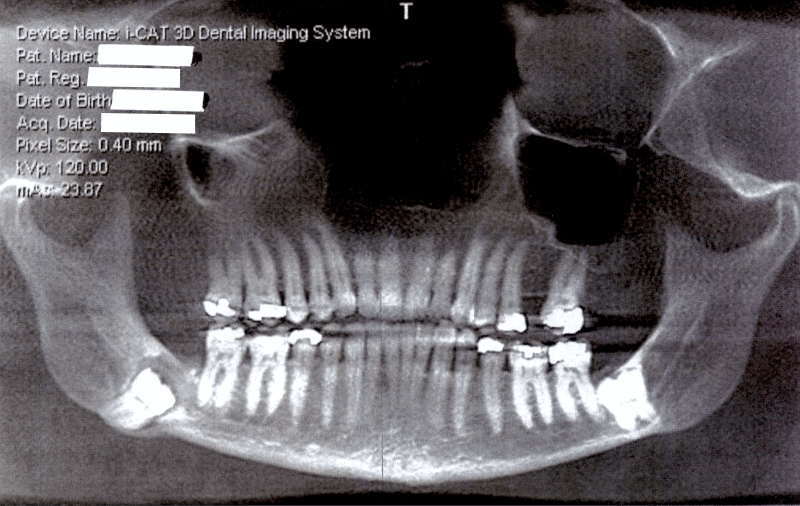

A Photo of Impacted Wisdom Teeth

In 2003, removing this wisdom tooth in a 50-year old would be as follows:

• Removal of the impacted tooth

• 800mg Ibuprofen and (20) High Strength Pain-Killers

• Jaw wrap for post-op swelling

In 2023, multiple improvements have been made:

• Preoperative natural anti-inflammatory medications

• Preoperative initiation of Vega Recovery kit

• Use of PRF in the extraction site to minimize pain, swelling, inflammation

• Use of dentin autografting to promote bone growth on the back side of the second molar in front of the wisdom tooth

• Postoperative use of natural anti-inflammatory medications and Vega Recovery kit

• 800mg Ibuprofen and either (2) or (5) High Strength Pain-Killers